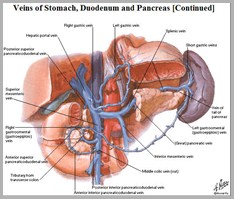

Normal anatomy and physiology

Placenta umbilical vein(ligamentum teres) hepatic sinusoid & ductusvenosus (ligamentumvenosum) portal vein IVC right atrium foramen ovale leftatrium left ventricle aorta systemiccirculation umbilicalarteries placenta

Fetal Circulation

From the umbilicus,umbilical vein passescephalad, slightly toright

Joins the left branch ofthe portal vein

The ductus venosusarises from the pointwhere the UV joins theleft portal vein

Ductus venosus entersIVC

UVC should be justabove diaphragm whereIVC enters RA (T8-T9)

Umbilical arteriesare directcontinuation ofinternal iliacarteries

UAC will usuallyenter aorta viainternal iliac artery

UAC should thenpass up aorta,above diaphragm,between T6 and T9